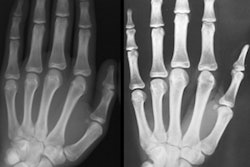

Bone age has typically been determined manually from hand x-rays by radiologists or pediatric endocrinologists, but this method is subjective and prone to reader variability. Danish company Visiana believes its automatic bone age assessment software can do the job better and faster.

Visiana's BoneXpert software provides automatic age analysis from standard hand radiographs in five seconds. And a number of research studies have shown Visiana's BoneXpert software to be more accurate and more precise than manual bone age ratings, according to CEO Hans Henrik Thodberg, PhD.

BoneXpert determines the bone age of 13 bones and forms an overall average using the Greulich-Pyle bone age standard. Because that standard is based on pre-World War II Caucasian children, however, BoneXpert also computes ethnicity-dependent bone age standard deviation scores to enable clinicians to assess a child's maturation, Thodberg said.